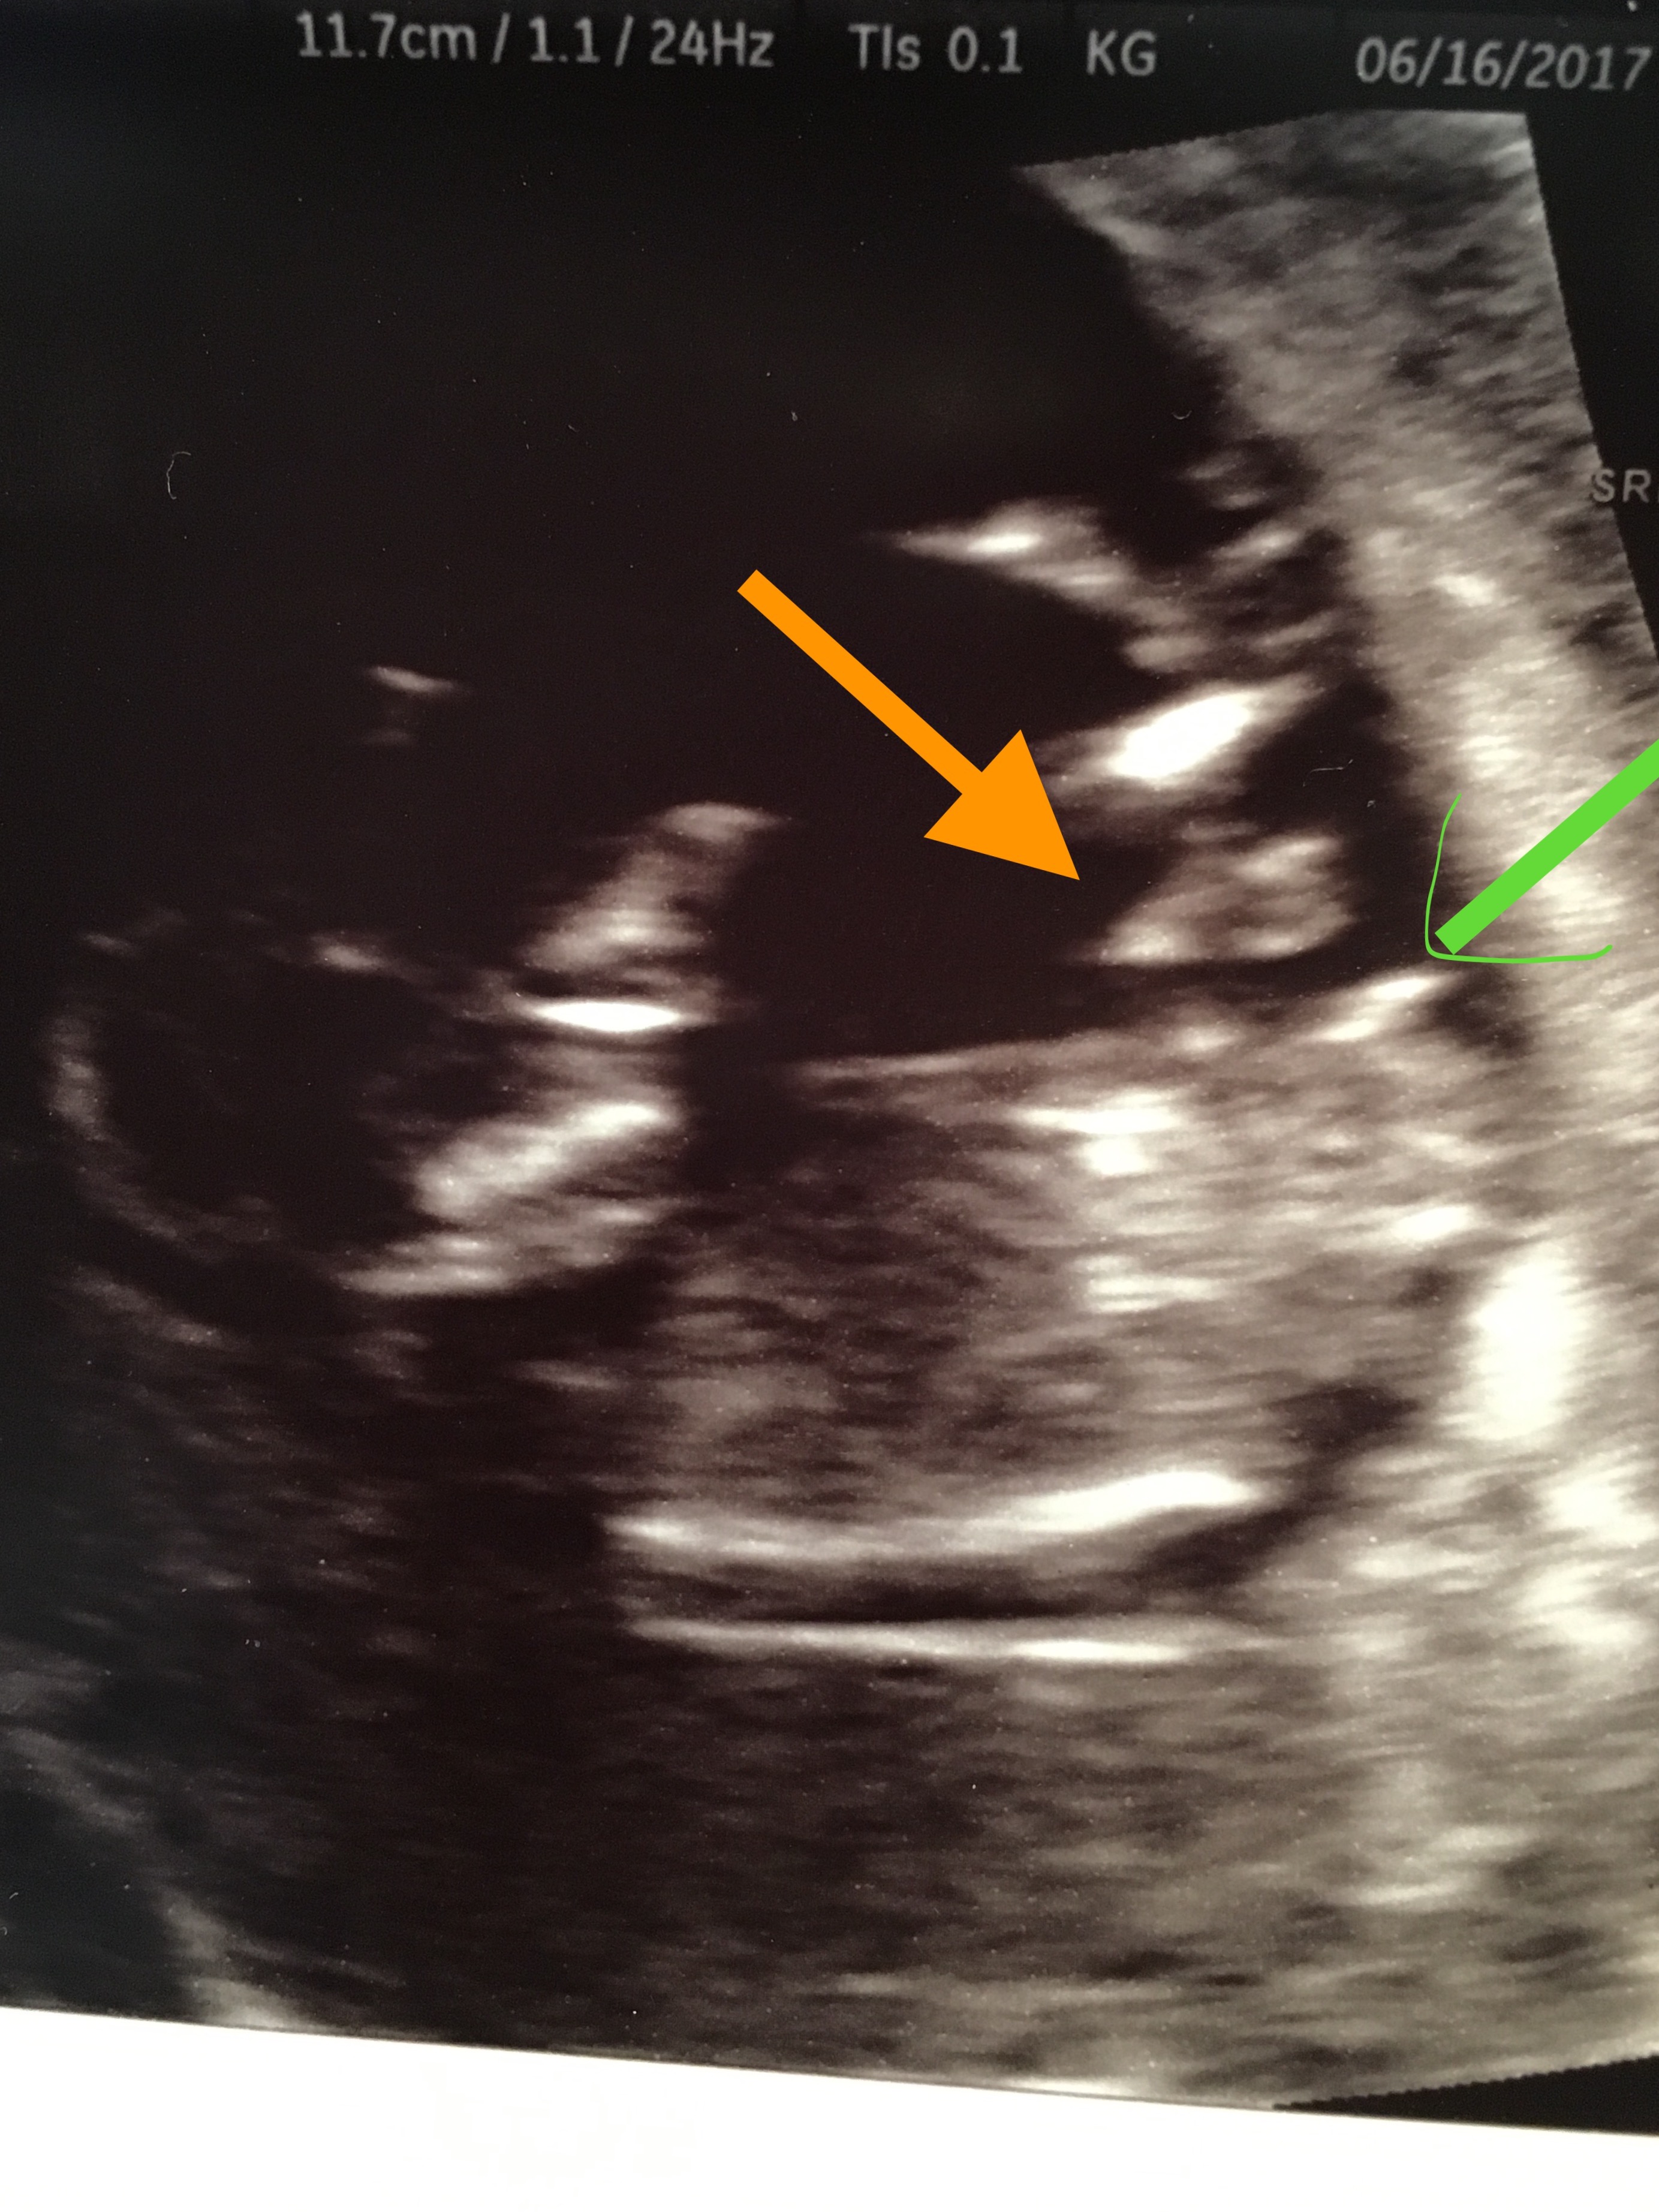

I think I may have finally found a picture that shows the nub? Thinking it's by the green arrow and the orange arrow points to the umbilical cord? If I'm right, any guesses?!? Thanks!

I'm not sure if the green arrow shows a nub or cord. Could be a boyish nub, could be a cord. Sorry!

I know, they're so close together it's tough to tell. Thanks!